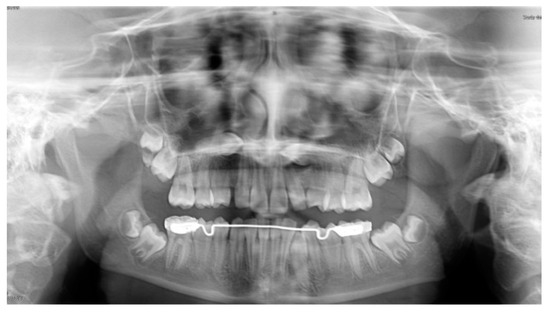

The MM2 was considered upright when the mesial marginal ridge was above the distal contours of first mandibular molar (MM1) (Figure 3).

Figure 3.

Post-treatment panoramic radiograph showing the correct inclination of 3.7 before miniscrew removal.